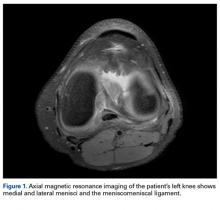

Radiographs taken the day of the first clinic visit showed no acute osseous abnormality. Magnetic resonance imaging (MRI) showed complete disruption of the proximal fibers of the ACL ( Figures 1, 2 ).

Also observed was a small oblique tear of the body of the lateral meniscus with slight blunting of the anterior horn of the medial meniscus, which may have been related to a small tear. A pivot-shift contusion pattern with impaction fracture of the lateral femoral condyle was also appreciated. There were no definite cartilage defects identified.

The medial and lateral menisci typically are separate fibrocartilaginous structures acting as a cushion for the knee, but normal variant connections between the structures have been described. These connections include the anterior transverse meniscal ligament, the posterior transverse meniscal ligament, and the medial and lateral oblique meniscomeniscal ligaments. 3 In the present case, a medial oblique meniscomeniscal ligament was identified. Its path between menisci was traceable on coronal and axial views. Video taken during arthroscopy also clearly showed its path and its relationship to other structures in the knee. To Dr. Flanigan’s knowledge, this ligament was not previously described with video. It is important to distinguish this ligament from a horizontal tear of the meniscus, given the potential for misinterpretation on MRI. A horizontal tear is a degenerative change that often occurs in older patients. Our patient was 18 years old at time of injury. In addition, the surface of his lower meniscus was smooth, whereas in a tear the edge is irregular and discontinuous. Dr. Flanigan prefers to leave this ligament intact unless resection would provide better visualization during arthroscopy. His reasoning is that the functional characteristics of the ligament are not well understood.